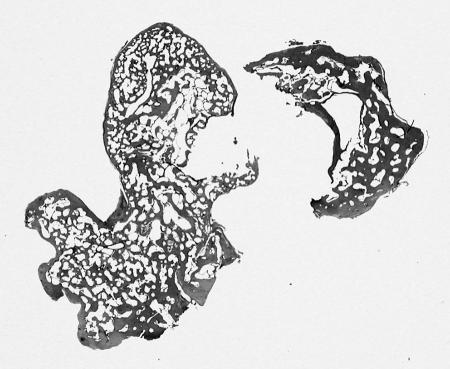

Figure 5.

Low–power magnification of a hematoxylin– and eosin–stained section showing a mass consisting of a thin cortex of normal lamellar bone with a medullary region of well–organized trabeculae with sparse osteoblastic rimming.